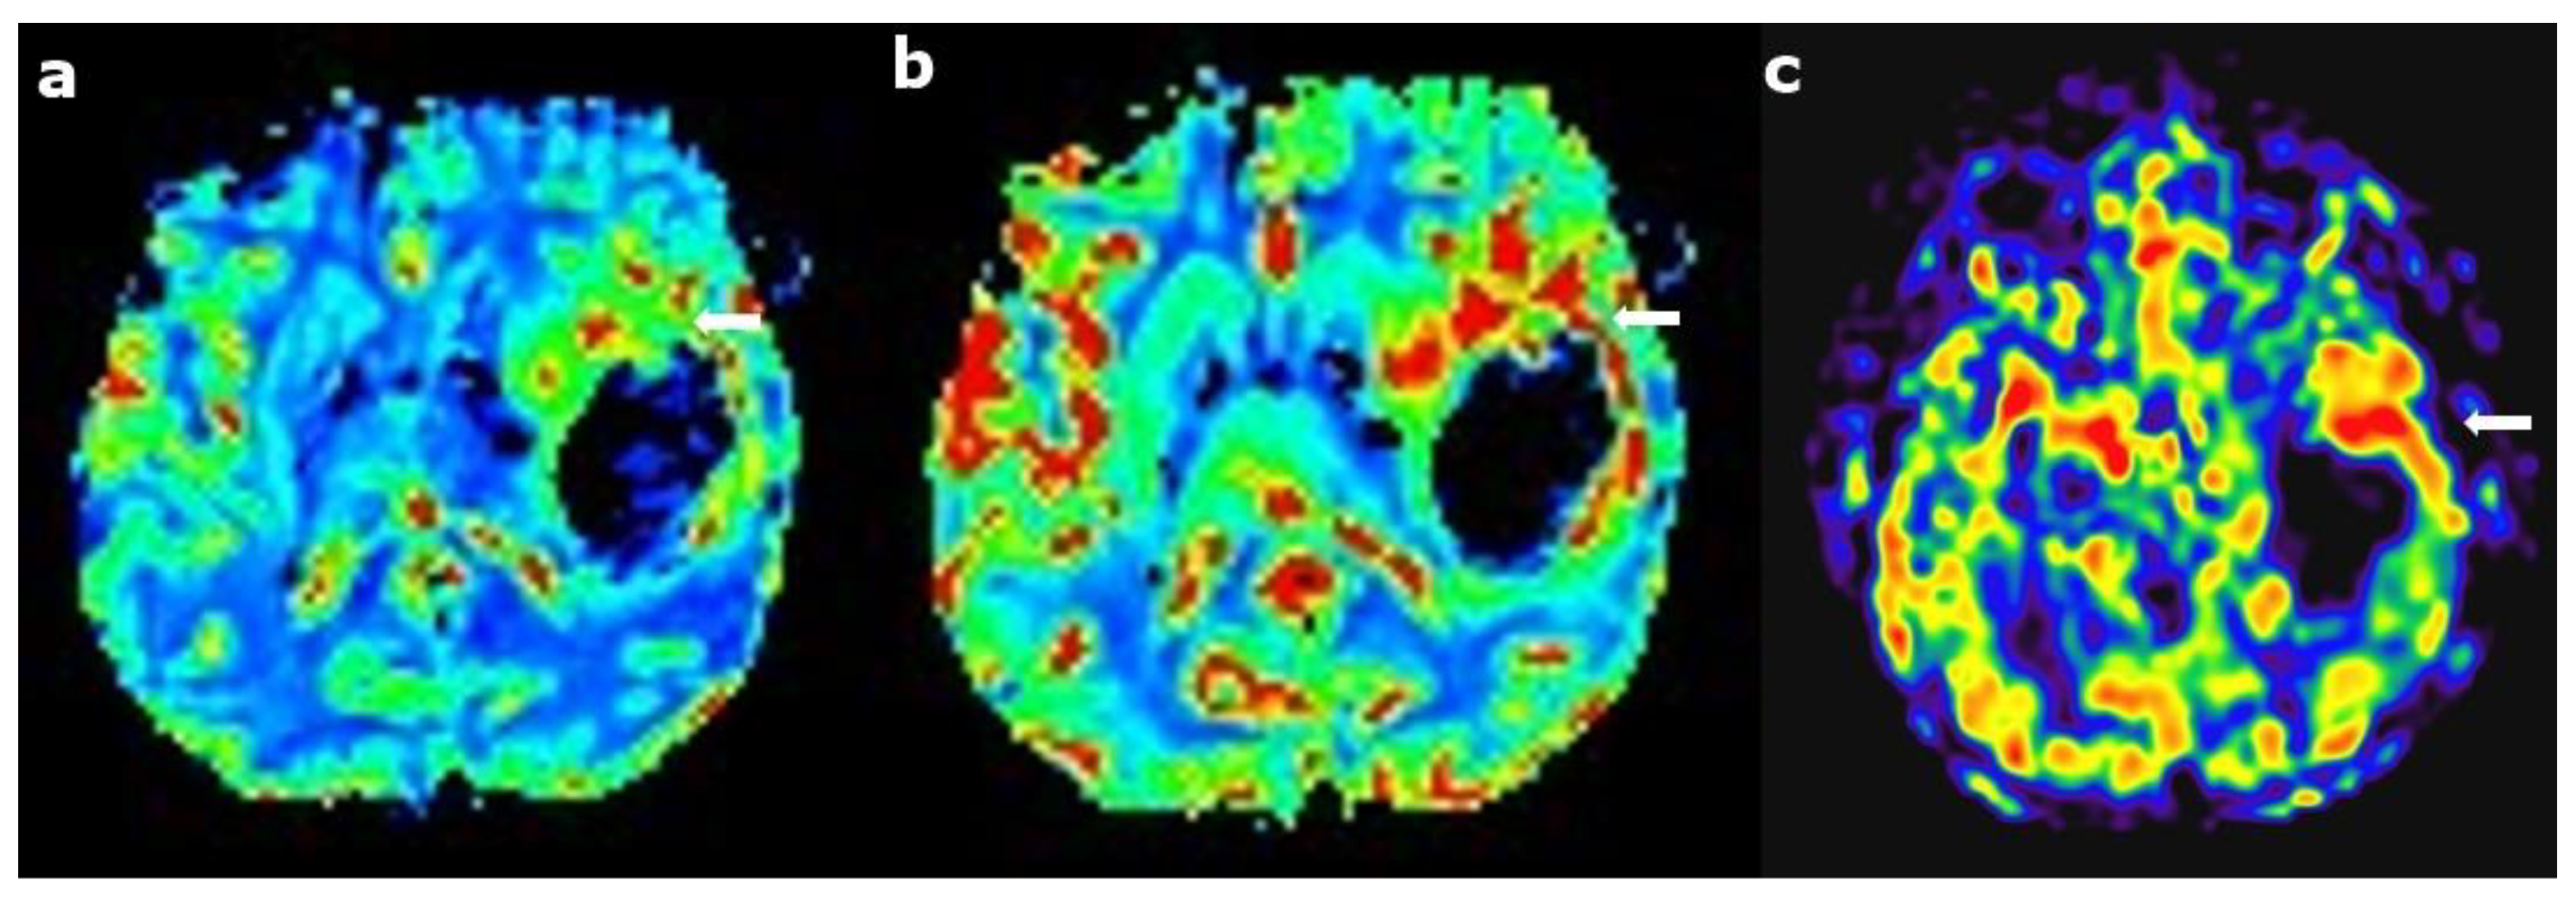

2.3. Perfusion Imaging

2.4. Dynamic Susceptibility Contrast Perfusion

2.6. Arterial Spin Labeling

5.1. Radiation Necrosis Versus Tumor Recurrence

5.2. Pseudoprogression